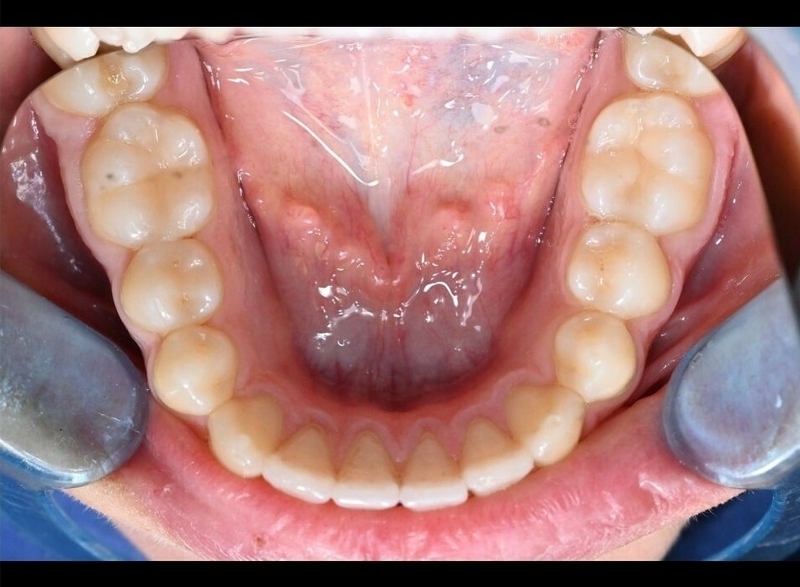

Cas 2 - Orthodontie par aligneurs invisibles

Avant